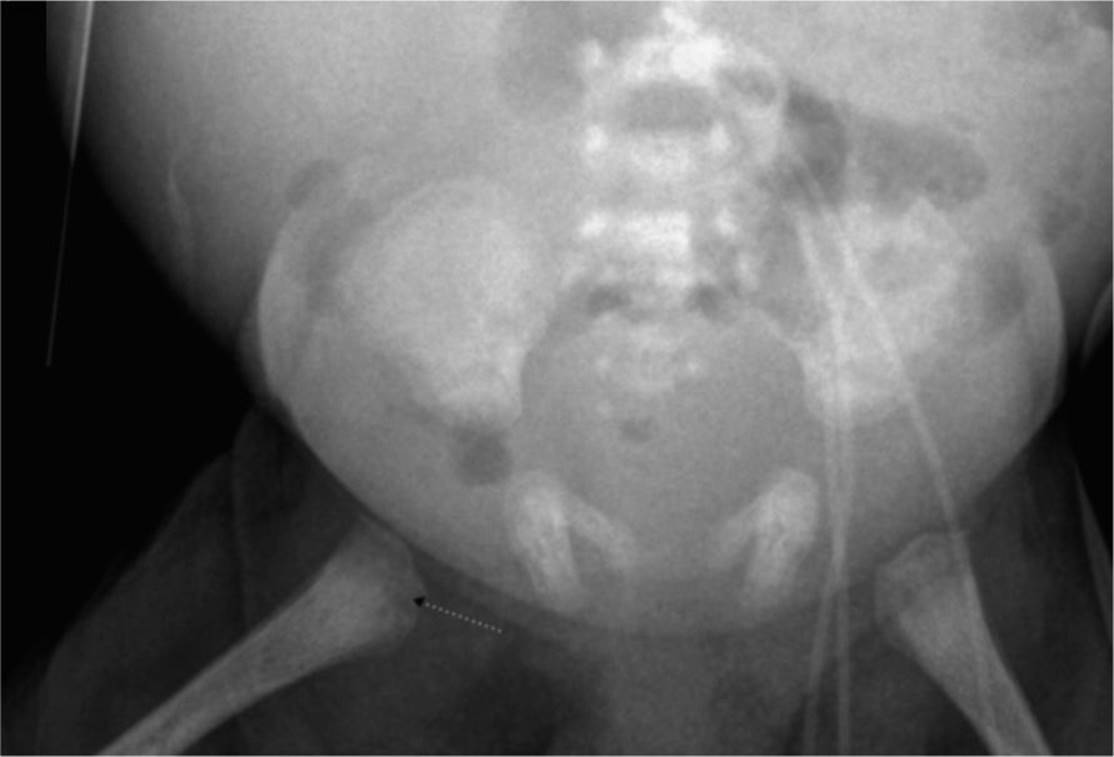

During the assessment, a rash noted on the mothers hands strongly suggested the infant’s diagnosis (Figure 15-1). Radiographs of the infant’s humerus (Figure 15-2) and femur (Figure 15-3) were also consistent with the diagnosis. The infant was admitted to the neonatal intensive care unit for additional diagnostic testing and treatment.

FIGURE 15-3. There are areas of metaphyseal lucency in the proximal femur.

The mothers’ hand revealed a pink, elliptical macules (Figure 15-1); the central area was darker than the periphery, which blended into the surrounding skin. The reddish hue, due to localized hyperemia, is characteristic of early secondary syphilis. Laboratory testing was significant for an RPR of 1:8 in the mother and 1:64 in the baby. These positive tests were confirmed with a positive Treponema pallidumparticle agglutination (TP-PA) assay. The infant received a lumbar puncture to evaluate for neurosyphilis. CSF protein and cell count were normal and CSF Venereal Disease Research Laboratory (VDRL) test was 1:8. She had a liver ultrasound that showed a homogenous enlarged liver and spleen with a normal gallbladder. The chest radiograph was normal. However, long-bone radiographs revealed metaphyseal lucencies involving the proximal humerus (Figure 15-2) and femur (Figure 15-3) that were consistent with the diagnosis of congenital syphilis. Testing for other TORCH infections as well as hepatitis B and C and HIV was negative. Given the presence of a positive RPR and TP-PA in both the mother and baby, in conjunction with the clinical findings of lymphadenopathy, jaundice, hepatosplenomegaly, and metaphyseal dystrophy, the patient was diagnosed with congenital syphilis.

The infant displayed many of the clinical features consistent with early congenital syphilis, including jaundice, hepatosplenomegaly, thrombocytopenia, rash, “snuffles,” pseudoparalysis, and metaphyseal dystrophy of the humerus and femur.